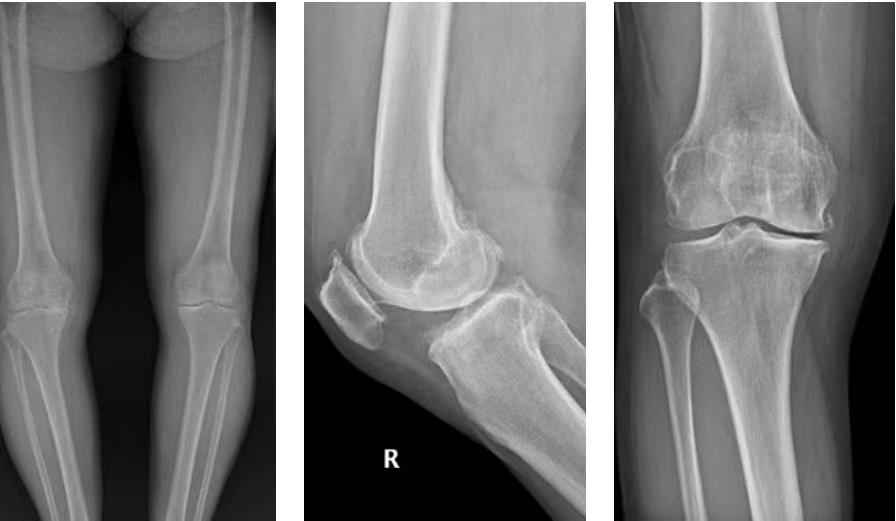

手术前,医生先通过CT扫描生成3D骨骼模型,帮助医生制定手术方案。同时,预判假体型号大小,使假体与患者骨骼完全匹配。

在广州和睦家医院就医时,陈女士被诊断为膝关节骨性关节炎,接诊的骨科刘宁主任建议陈女士选择用MAKO机器人辅助完成单髁关节置换术,解除疼痛困扰的同时,还能最大限度地保留骨量、本体感觉,以及关节功能。

机器人手术精准 误差控制在1°和1毫米以内